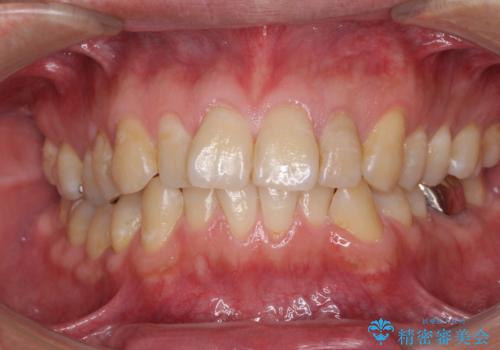

前歯のデコボコを改善 インビザライン矯正

担当医 藤巻太一朗